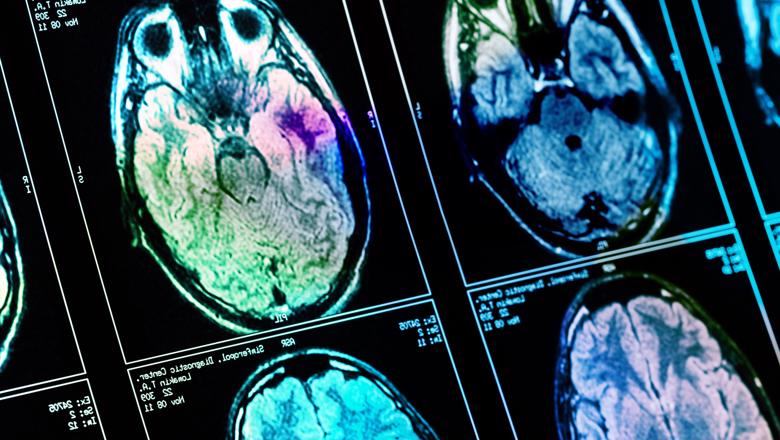

Una de las enfermedades más devastadoras que puede enfrentar un ser humano son los tumores cerebrales. No solo por la dificultad que conlleva combatir cualquier tipo de cáncer, sino por la zona que está afectada, ya que el cerebro es el órgano más delicado y más importante en el funcionamiento de nuestro organismo. Es por esto que una de las prioridades de la medicina enfocada en el cerebro ha sido desarrollar nuevos tratamientos que puedan combatir de tú a tú el cáncer, algo que no ha podido lograrse durante las últimas décadas.

Pero finalmente hay buenas noticias en esta lucha ya que un estudio pionero de la Universidad de Tel Aviv erradicó eficazmente el glioblastoma, un tipo de cáncer cerebral altamente letal. Los investigadores lograron el resultado utilizando un método que desarrollaron basándose en su descubrimiento de dos mecanismos críticos en el cerebro que favorecen el crecimiento y la supervivencia de los tumores: uno protege a las células cancerosas del sistema inmunitario, mientras que el otro suministra la energía necesaria para el rápido crecimiento del tumor.